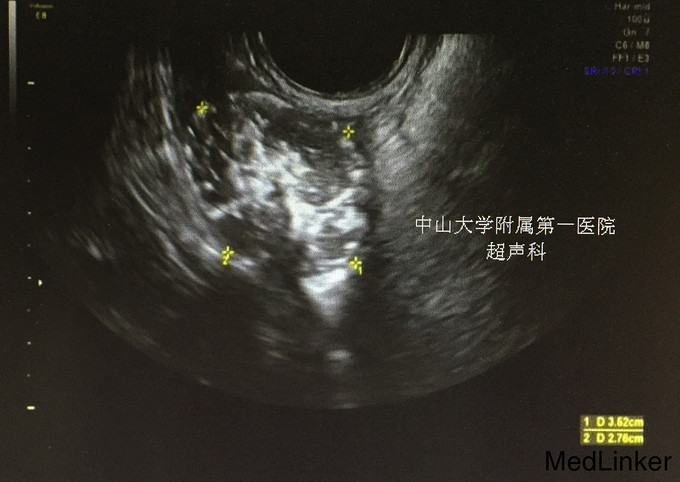

查体:生命体征平稳;双侧乳腺发育稍差。妇检:外阴呈女性生殖特征,阴蒂肥大,可见尿道开口;阴道外口可见,无性生活史,未内诊。肛查示子宫小,盆腔右侧可及包块。 辅查:2015-08-15妇科B超示:子宫小,左侧卵巢内未见明显卵泡结构;右侧附件区囊性肿块,待排畸胎瘤(43mm*30mm)。 2015-08-24查染色体示46XY,t(4;20)(q27;p13)。 2015-09-28我院查盆腔MR示双侧附件肿块,性质待定,考虑卵巢来源;阴茎发育短小,子宫小,符合双性畸形改变。

诊断:两性畸形 治疗:请我院资深超声科主任医师复查妇科B超示双侧两性母细胞瘤可能。查腹部MR:1.右侧附件区囊实性肿块,左侧附件区实性肿块,性质待定,考虑卵巢来源肿瘤。 2.阴茎发育短小,子宫稍小,符合双性畸形改变。 3.双侧肾脏及输尿管、膀胱MRI扫描未见异常。 4.上腹部MRI扫描未见异常。 请儿科教授会诊,46XY性发育障碍,意见:女性表型含Y染色体者发生性腺恶性肿瘤可能性大,建议腹腔镜性腺切除。查皮质醇8AM正常及ACTH 8AM,均正常。行腹腔镜下双侧性腺肿瘤切除术+双输卵管切除术。术中冰冻结果:良性。